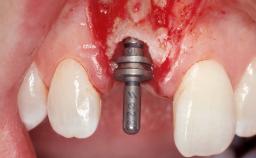

Immediate Flapless Placement of an Implant in a Maxillary Right Lateral Incisor Site

This 43-year-old male patient, a non-smoker, came to our practice because of a fracture of tooth 12 caused by a bicycle accident. Due to the combined para- and infrabony crown and root fracture, tooth extraction, and subsequent implant placement were suggested to the patient as the therapy of choice. The patient had high esthetic expectations with regard to the treatment outcome and asked for an immediate fixed provisional restoration. His individual esthetic risk profile summed up to a medium esthetic risk.

Placement Protocol Immediate implant placement

Tooth Site Maxillary incisor or canine

Socket Morphology Single-root socket

Socket Integrity Sufficient, with intact bone walls

Bone Volume Sufficient, with intact walls